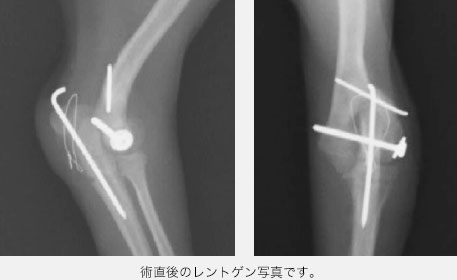

成犬の骨折ではプレート・スクリュー法という、ガッチリとした強固な固定を行いますが、仔犬の成長板骨折ではプレートを使用すると成長を妨げてしまうため、ワイヤーとスクリューを使った術式を用います。

骨折端が見えたところで、横方向にはスクリュー固定(ラグスクリュー法といいます)を行い、縦方向(骨が伸びる方向)にはワイヤーを使った方法を用いました。骨折端がピッタリとくっついているのを確認した後に、先ほど切断した尺骨の切断面を戻しワイヤーにて固定しました。

術後は少しずつ足を使うようになり、2ヶ月ほどたって骨が癒合し、スクリューとワイヤーを全て抜去しました。